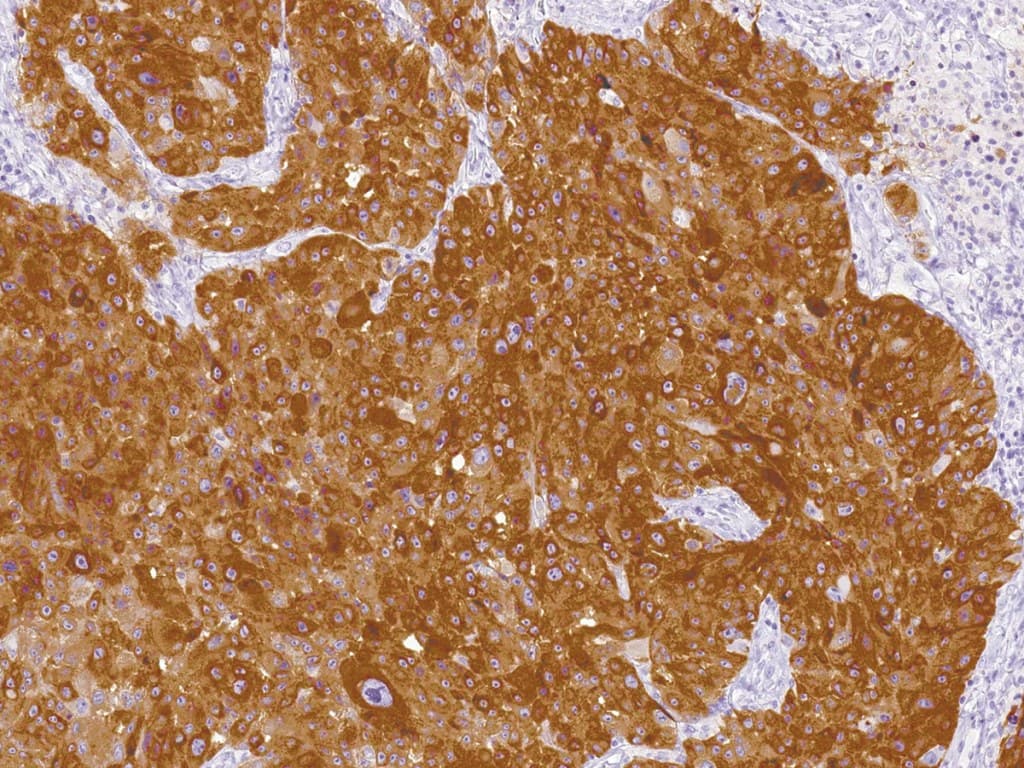

MART-1, noto anche come Melan A o Melanoma Antigen Recognized by T Cells 1, è un antigene proteico che si trova specificamente sui melanociti della pelle normale, della retina e dei nevi, e non in altri tessuti normali. È una proteina di membrana di tipo III con un peso molecolare di 22-24 kDa. È presente nel reticolo endoplasmatico (ER) e nella rete trans-Golgi (TGN). MART-1 è una proteina del lineage dei melanociti.

MART-1 etichetta sia i melanociti normali che le cellule malate con differenziazione melanocitaria. È utile per la diagnosi dei tumori con differenziazione melanocitaria, in particolare del melanoma metastatico. L'identificazione di MART-1 apre inoltre la possibilità di sviluppare immunoterapie per i pazienti affetti da melanoma. L'anti-MART-1 (Melan A) è quindi utile come marcatore dei tumori melanocitari e come ausilio nella diagnosi dei melanomi metastatici.